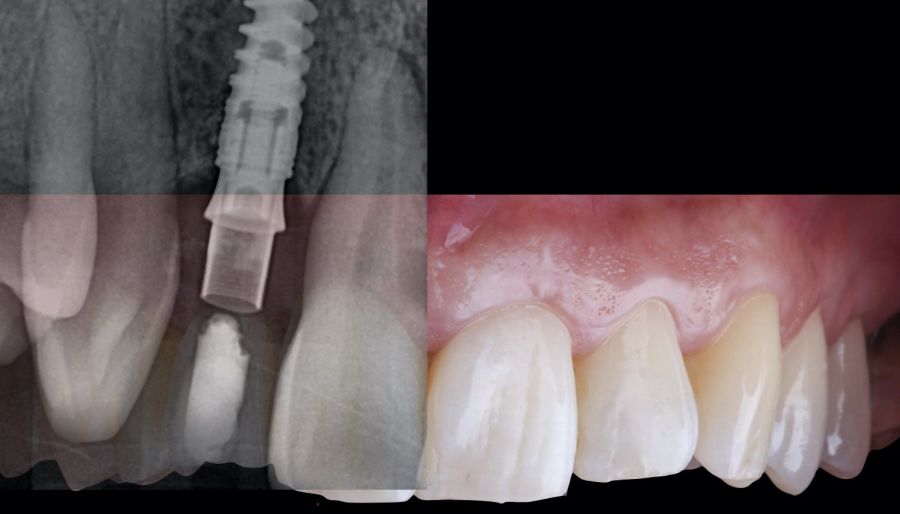

-Fase I: se realizó la extracción atraumática del resto radicular 1.2 y se efectuó un legrado del tejido de granulación. A continuación, se realizó el relleno del alveolo mediante un injerto óseo bovino inorgánico (0,25-1mm) combinado con fibrina autóloga rica en plaquetas y leucocitos. Finalmente, se suturó aproximando los bordes mediante 4 puntos simples desde el margen mucoso vestibular al palatino. Después, la paciente siguió usando su prótesis parcial removible como restauración provisional (Figura 1).

-Fase II: la cicatrización transcurrió sin complicaciones. Tras 5 meses de la cirugía de preservación alveolar, se planificó la cirugía implantológica guiada en posición 1.2 (Figura 2). Para ello, se utilizaron un archivo DICOM procedente de la tomografía computarizada de haz cónico (CBCT) y el archivo STL procedente del escaneado mediante un escáner óptico intraoral. Con esta información se construyó una férula quirúrgica de soporte dental (Figura 3). La férula quirúrgica se ancló sobre los dientes y guió la realización del lecho implantario y la colocación del implante. La técnica quirúrgica de cirugía guiada consistió en una cirugía con colgajo, preparando e insertando el implante (3,5 x 11,5 mm) según el protocolo estandarizado de cirugía guiada Nobel Active® (Nobel Biocare AB, Gothenburg, Sweden). Una vez colocado el implante 1.2, se obtuvo un injerto gingival compuesto de epitelio y tejido conectivo de la mucosa masticatoria palatina. A continuación, se realizó la desepitelización de la capa superficial de dicho injerto fuera de boca mediante una hoja de bisturí 15C con la finalidad de obtener un injerto de tejido conectivo de la capa subyacente18.

El injerto desepitelizado se insertó y posicionó por vestibular y oclusal mediante un punto colchonero horizontales utilizando sutura 5-0 no reabsorbible (Figura 4)19.